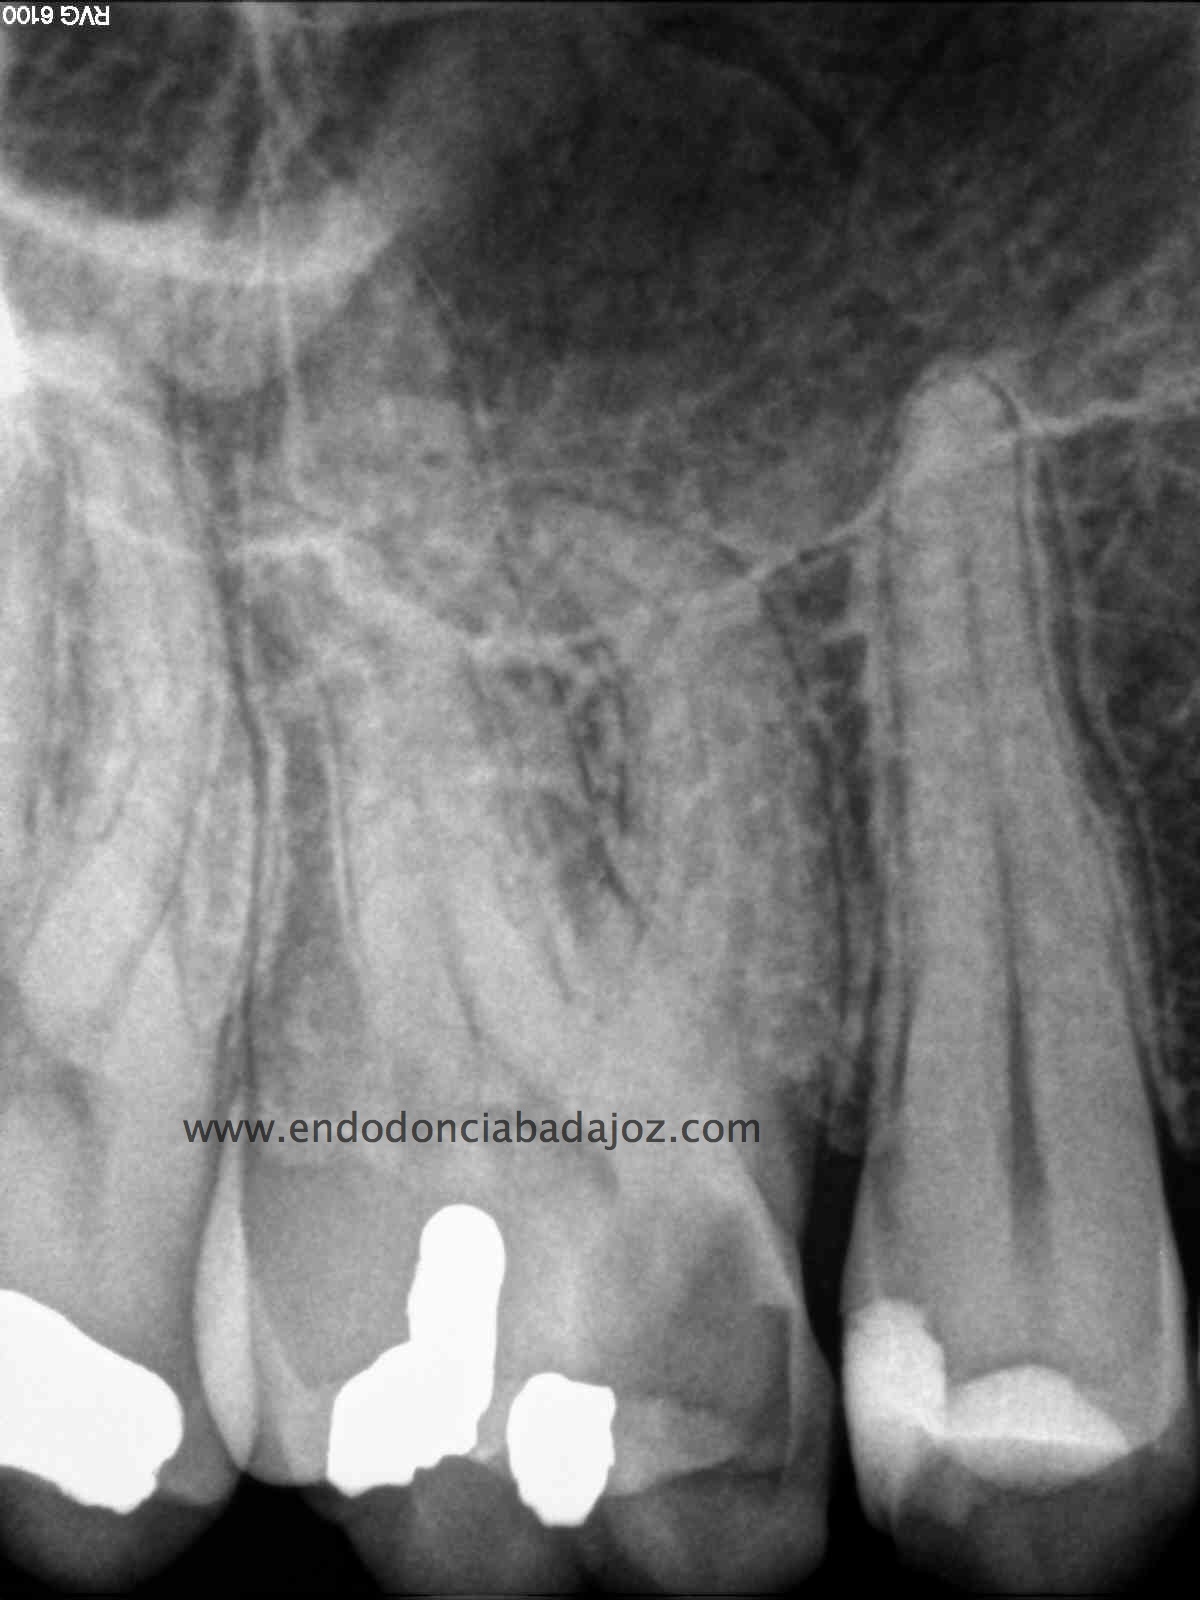

El sistema de obturación que usamos fue condensación vertical por ola de continua:

(down pack)

Hicimos el backfilling con la pistola Obtura II: